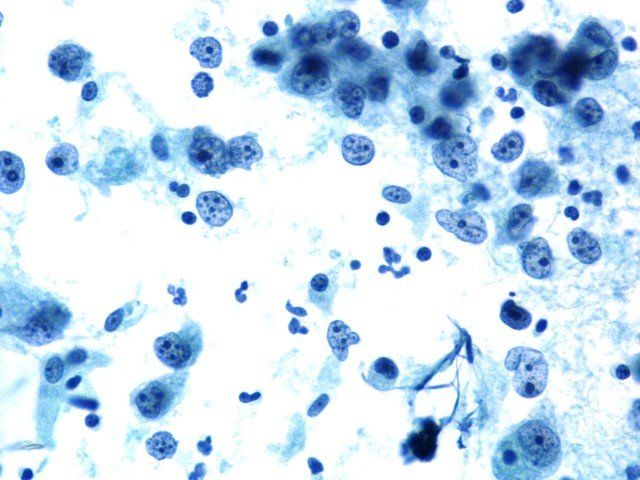

Fluid Romanowsky - shema dijagnostičke citologije.

Ovaj preparat pokazuje izvrsno bojenje i jezgre i citoplazme. Na procjeni je postignut rezultat 9/10.